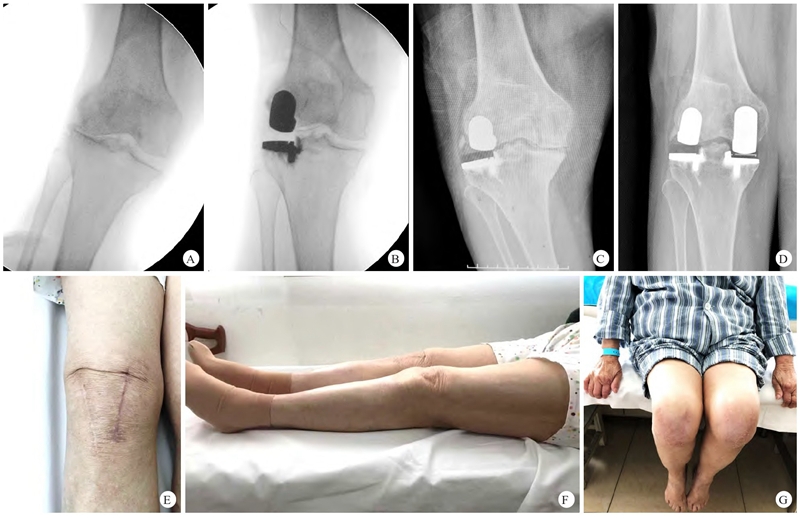

图3 患者,女,64岁,右膝关节外侧间室OA进行UKA,术后30个月右膝关节内侧间室进展OA,K-L 4级,采用UKA进行翻修

A. 第一次入院术中右膝关节外翻应力位透视显示外侧间隙完全消失,K-L 4级;B. 术中透视外侧假体位置良好,无松动,内侧间隙正常;C. UKA 术后30个月内侧间室进展OA,关节间隙明显狭窄;D. 第二次入院内侧间室进展OA采用UKA治疗,术后3个月右膝关节正位X线片显示股胫假体位置满意,内侧间隙恢复正常,股胫力线内翻矫正;E~G. 第二次术后3个月外侧髌旁手术直切口(长9 cm),内侧陈旧手术切口(长7 cm),两切口均愈合好;下肢完全伸直,无屈曲畸形;膝关节屈曲活动恢复满意,最大可至120°。